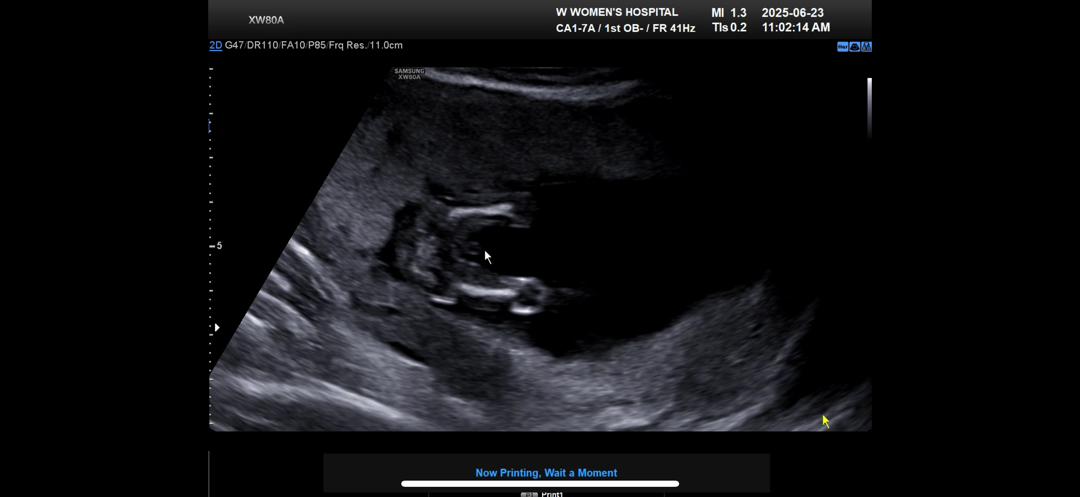

14주 4일 아들같은데 다시 확인하자!

아들일가요..? 반전 있을까요?